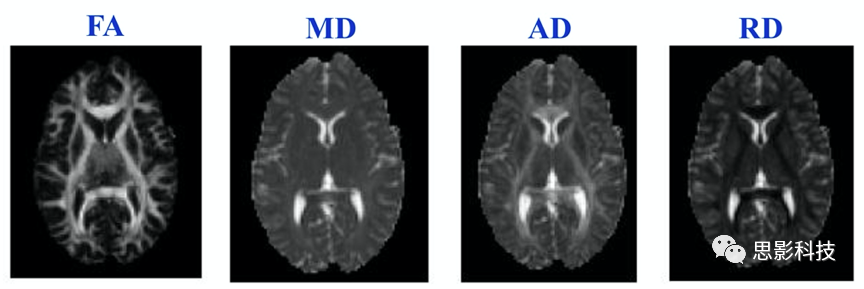

3.dMRI指標(biāo)。dMRI(彌散磁共振)數(shù)據(jù)經(jīng)頭動(dòng)渦流校正、張量擬合等預(yù)處理步驟后,可得到FA、MD、AD、RD等指標(biāo)。以上指標(biāo)可以在體素水平計(jì)算。

圖示.彌散影像指標(biāo)。